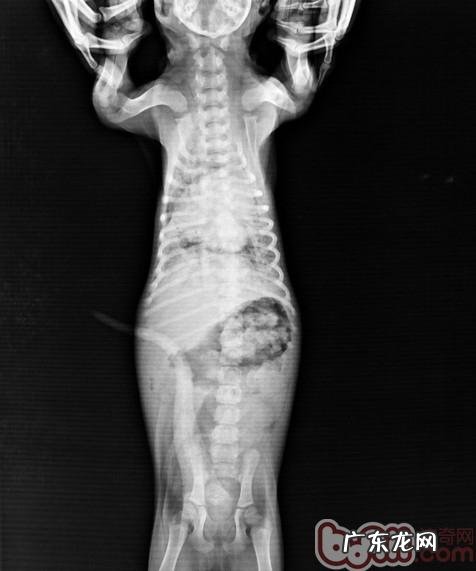

传染性疾病清查内未见异常 。白血球低(WBC)大幅度上升,在其中嗜中性化白细胞计数很多提升,且有很多核左移状况 。X射线检查右边肺泡有大面积黑影地区 。

X射线检查